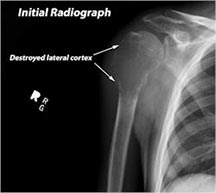

X-ray:

- Permeative lesion with indistinct border that is poorly marginated

- Osteolytic and expansile on X-ray with very little osteoid production

- No surrounding sclerosis

- May have Codman’s triangle and malignant appearing periosteal reaction in most cases

- Cortical destruction and soft tissue extension are common